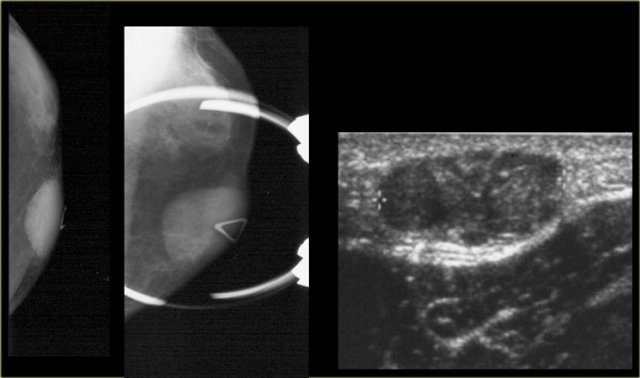

Epidermal inclusion cyst. T2WI with fat sat and pathology Epidermal inclusion cyst. T2WI with fat sat and pathology

On the left a T2W image demonstrating the cystic nature and the pathology specimen.